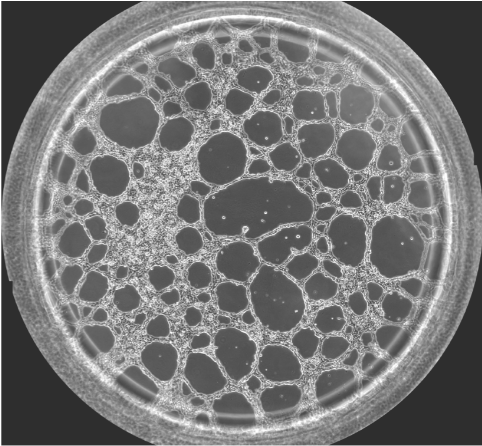

圖一 血管生成鏡檢圖

無論原發性腫瘤還是繼發性腫瘤,一旦生長直徑超過1~2 mm,都會有血管生成。這是由于腫瘤細胞自身可分泌多種生長因子,誘導血管生成。多數惡性腫瘤的血管生成密集且生長迅速。因此,血管生成在腫瘤的發展轉移過程中起到重要作用,抑制這一過程將能明顯阻止腫瘤組織的發展和擴散轉移。于是體外的血管生成實驗就能很好的模擬腫瘤的血管發生過程,并且適合研究藥物對這一過程的影響實驗。本實驗以HUVEC細胞為例,介紹這一實驗的詳細過程。